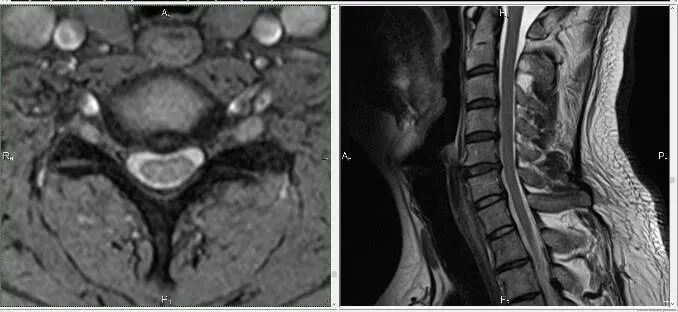

У этого пациента болела шея и плечо с левой стороны. Боль была очень интенсивная, он не спал ночью. При движении шеей сильная боль простреливала в руку. Обезболивающие препараты не помогали. Его хотели оперировать. Это делать было опасно, поскольку были признаки спинального стеноза (сужения канала позвоночника). Причина боли – спондилез: костные разрастания на шейных позвонках, которые суживали отверстие, через которое проходит левый шейный пятый корешок.

Чтобы снять боль в шейном отделе позвоночника и боль в руке, пришлось расширить это отверстие за счет оптимизации биомеханики позвоночника. Операция не потребовалась, пациенту стало легче.